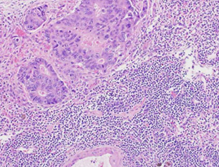

Σχήμα 2 . Μεγαλοκυτταρικό νευροενδοκρινικό καρκίνωμα, θετικό για χρωμογρανίνη Α, και μέτρια διαφοροποιημένο αδενοκαρκίνωμα σε εικόνα σύγκρουσης.